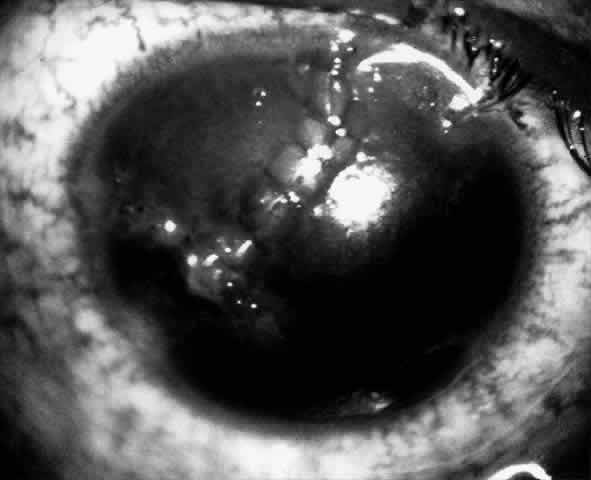

Children who have traumatic cataracts with corneal lacerations are well served by this procedure because the injury often destroys the capsular support that can be used to stabilize an intraocular lens.16–18 The epikeratophakia graft provides structural support for the weakened cornea and minimizes the induced irregular and regular astigmatism, in addition to correcting the optical error (Figs. 3 AND 4).

Fig. 3. Lacerated cornea with a hyphema. (Morgan KS, Ellis GS, Marvelli TL, Arffa RC: Epikeratophakia in children with traumatic cataracts. J Pediatr Ophthalmol Strabismus 23: 108–113, 1986)